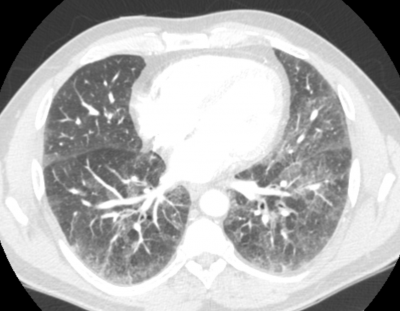

Age: 57

Sex: Male

Indication: Shortness of breath

Sample ReportDiffuse bilateral fine reticular opacification most likely representing chronic changes of interstitial lung disease. Recommend nonemergent interstitial lung disease protocol chest CT for further evaluation.

Bilateral subcentimeter pulmonary nodules, which can also be further evaluated with CT.